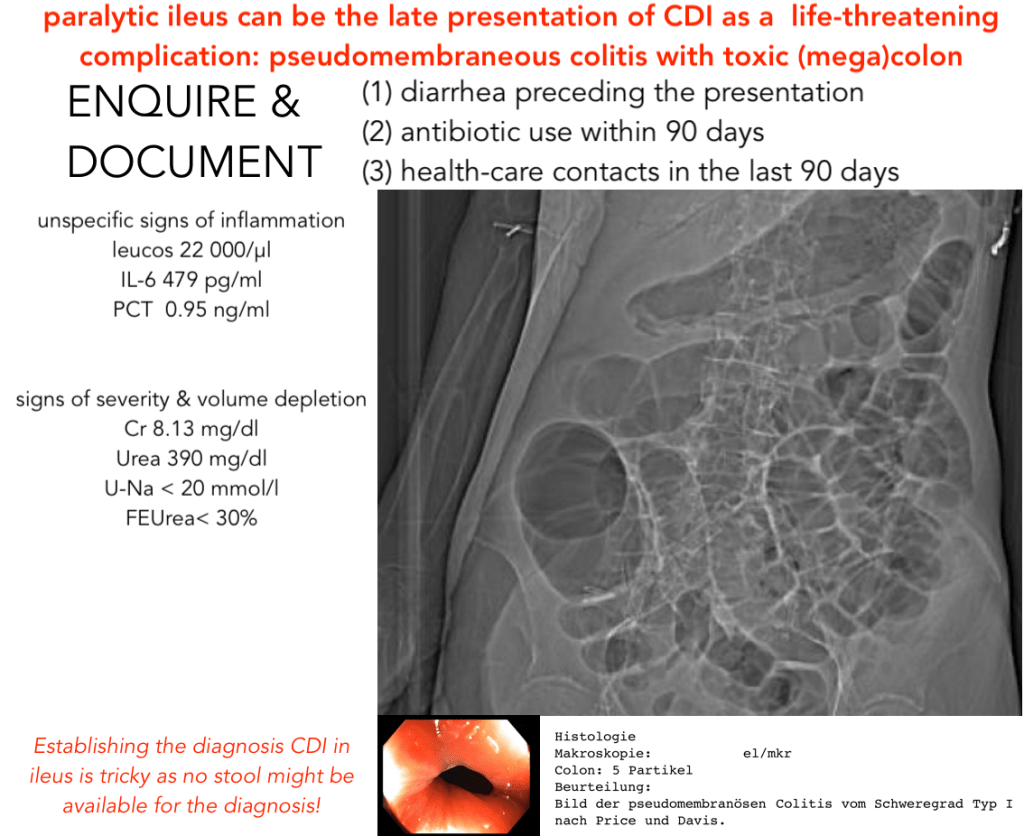

PEARLS CDI